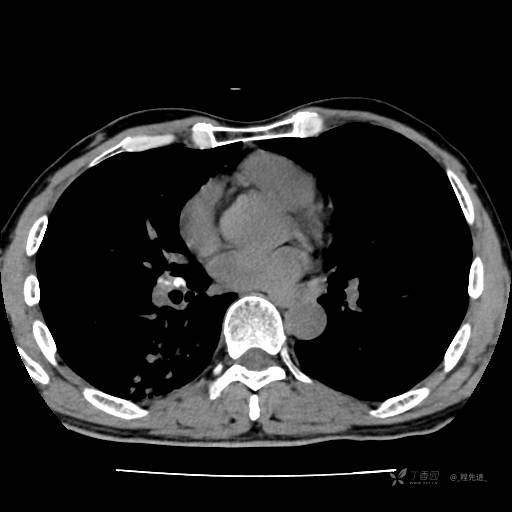

2月特别精彩病例|咳嗽、咳痰20余天,典型病例分享【结果已公布】

患者年龄:51岁

主诉:咳嗽、咳痰20余天

简要病史:20余天前开始出现咳嗽、咳痰症状,阵发性刺激性咳,白色粘痰,不易咳出,无发热,无咯血,无恶心、呕吐等不适,未诊治,咳嗽、咳痰症状持续存在。

体格检查:T:36.3 ℃ P:79 次/分 R:20 次/分 BP:128/64 mmHg,神志清楚,呼吸平稳,双肺呼吸音粗,右下肺闻及细湿性啰音。心率79次/分,节律整齐,各瓣膜听诊区未闻及病理性杂音。腹部未见异常,双下肢无水肿。

辅助检查:我院门诊胸部CT示:如下。心电图:窦性心律;正常心电图。